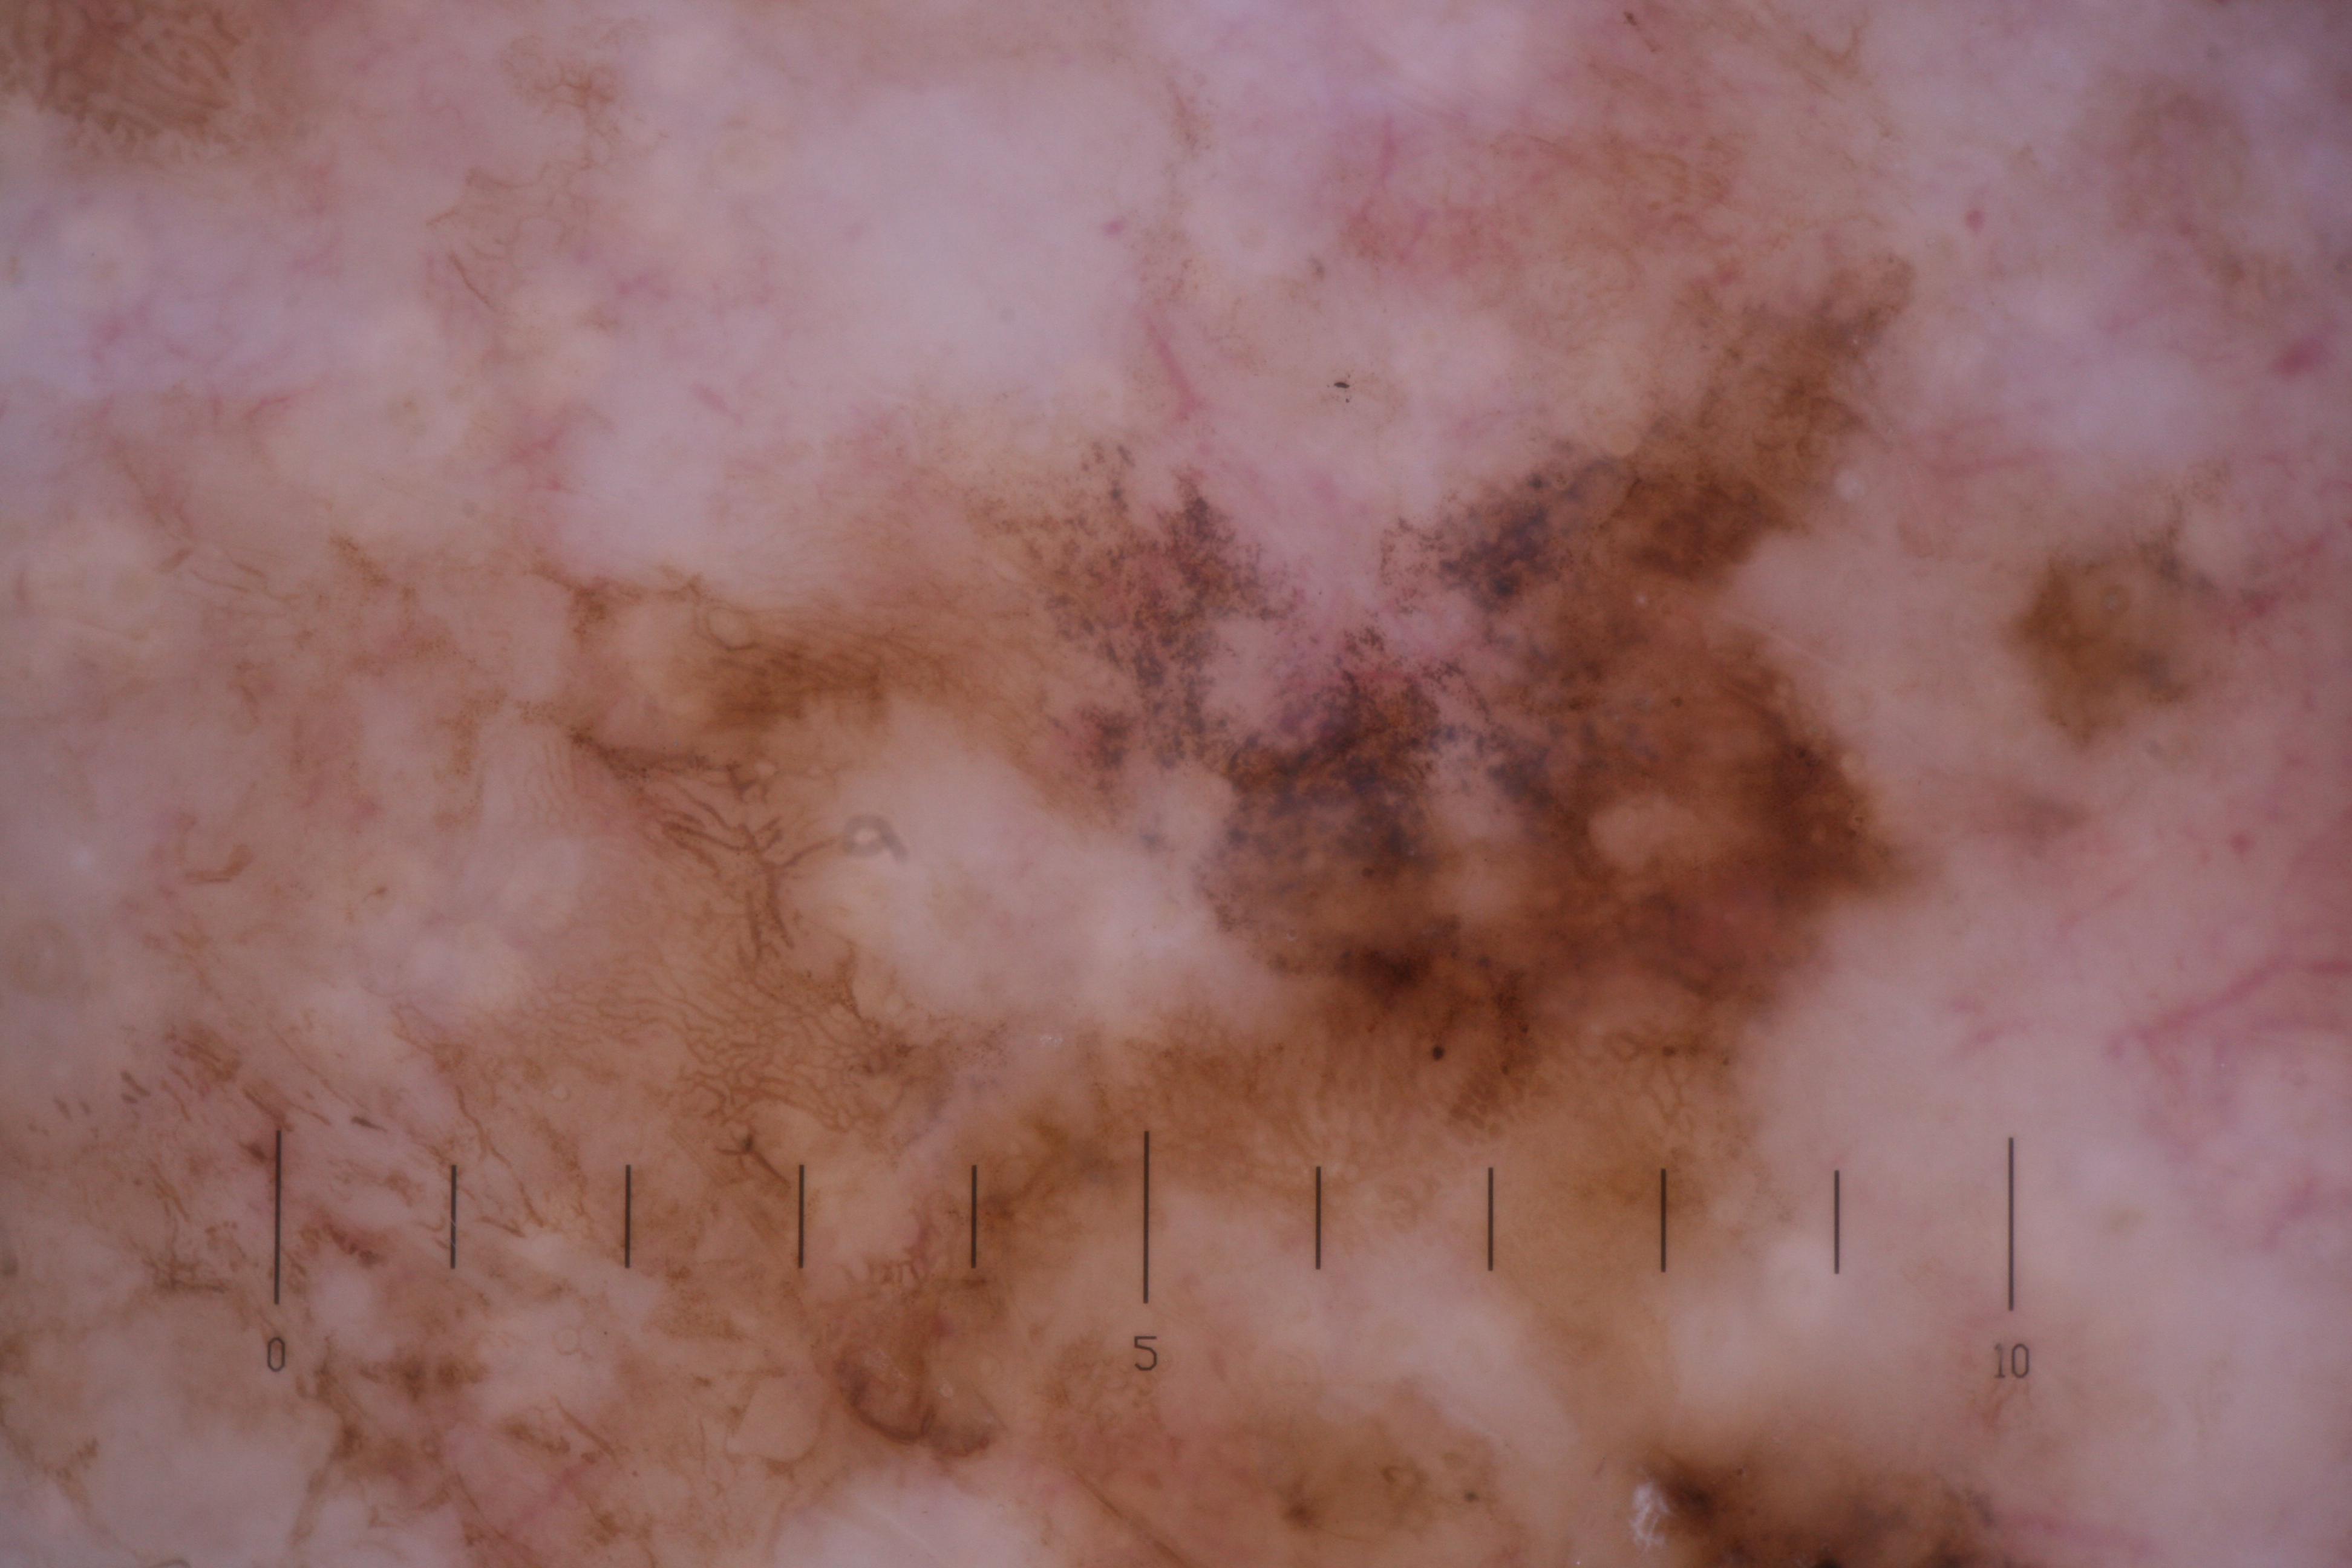

{

"age_approx": 75,

"anatom_site_general": "head/neck",

"concomitant_biopsy": true,

"diagnosis_1": "Malignant",

"diagnosis_2": "Malignant melanocytic proliferations (Melanoma)",

"diagnosis_3": "Melanoma, NOS",

"diagnosis_confirm_type": "histopathology",

"fitzpatrick_skin_type": "II",

"image_type": "dermoscopic",

"lesion_id": "IL_3161369",

"melanocytic": true,

"patient_id": "IP_8585290",

"sex": "male"

}